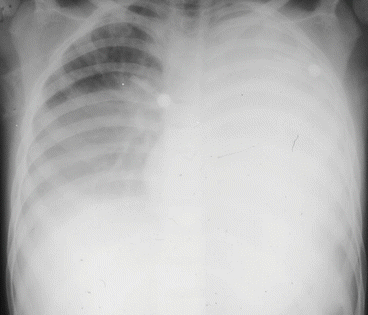

22+ Sickle Cell Anemia Sc Pictures. It is caused by an inherited abnormal hemoglobin that decreases life expectancy. Infarctions in the spleen, kidneys, bone, cns, and other organs are common and cause progressive loss of organ function and acute and chronic pain in affected parts of the body.

These sickle shaped cells get stuck together easily, and block off small blood vessels. People with sickle cell anemia have an increased risk of serious infection, and fever can be the first sign of an infection. Related online courses on physioplus. Sickle cell anemia, hereditary disease that destroys red blood cells by causing them to take on a rigid 'sickle' shape.